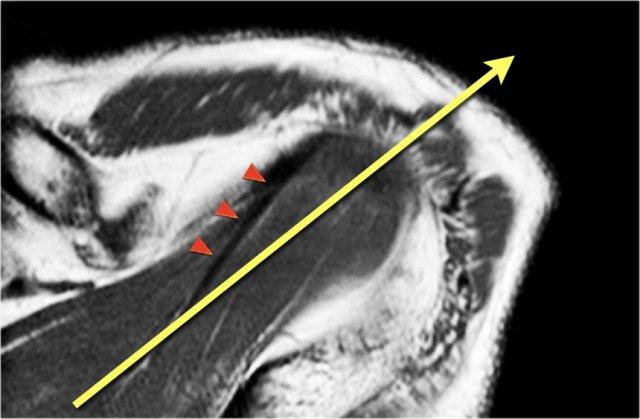

Trục của gân cơ trên gai

Gân cơ trên gai là cấu trúc quan trọng nhất của chóp xoay và là vị trí thường gặp của bệnh lý gân và rách gân.

Rách gân cơ trên gai được quan sát rõ nhất trên các chuỗi chụp nghiêng vành và chuỗi ABER.

Trong nhiều trường hợp, trục của gân cơ trên gai (đầu mũi tên) xoay ra trước nhiều hơn so với trục của cơ (mũi tên vàng).

Khi lập kế hoạch chuỗi chụp nghiêng vành, tốt nhất nên tập trung vào trục của gân cơ trên gai.